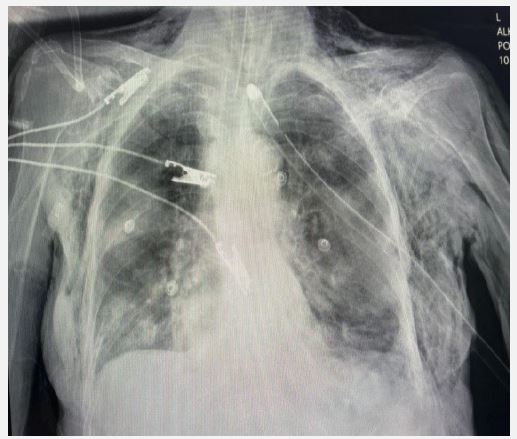

The patient was diagnosed with septic shock secondary to pneumonia and UTI. Management included broad-spectrum antibiotics, intravenous hydration, and vasopressor support for persistent hypotension. A left subclavian central venous catheter insertion for vasopressor administration was attempted but complicated by significant bilateral subcutaneous emphysema, though no pneumothorax was identified. A chest tube was inserted to manage the emphysema, with a post-procedure chest X-ray confirming appropriate placement (Figure 1). Over the next 48 hours, the subcutaneous emphysema resolved, but the patient’s hypotension persisted, and her clinical condition worsened. Despite intensive care measures, the patient succumbed to her illness after two days.

Figure 1: Chest X-ray displaying the left chest tube in place, bilateral subcutaneous emphysema, and no evidence of pneumothorax.